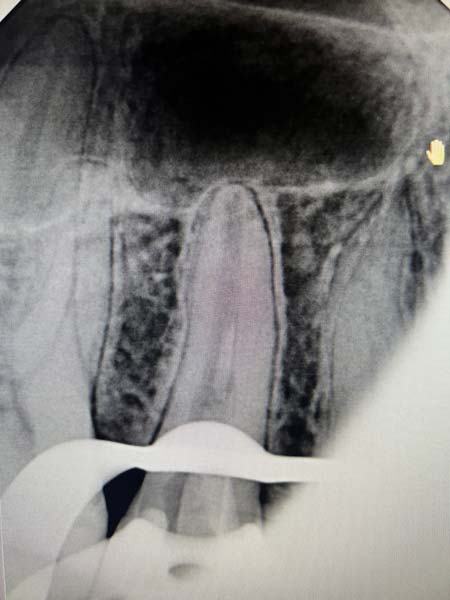

Менеджмент сепарованих ендодонтичних інструментів

"Менеджмент сепарованих ендодонтичних інструментів"

Як не ламати інструменти в кореневих каналах: причини та фактори ризику?

Сепаровані файли і прогноз ендодонтичного лікування: доказова база

Детальний розбір методів вилучення сепарованих ендодонтичних інструментів з кореневого каналу (з мікроскопом і без)

Коли ризик перевищує користь: в яких випадках вилучені інструменти ліпше не вилучати із кореневого каналу? Що робити з ускладненнями при вилученні сепарованих ендодонтичних інструментів?